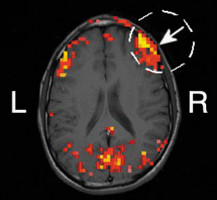

Researchers at the University of Illinois (UI; Champaign, IL) are exploring the use of frequency-domain near-infrared spectroscopy (NIRS) as a noninvasive diagnostic tool to study changes in human brain activity. In one experiment, they demonstrated a correlation between hemodynamic (blood-flow-related) signals at the surface of the brain obtained with both NIRS and functional magnetic resonance imaging (MRI)—the standard technique used in brain activation studies. Based on the results, UI physics professor Enrico Gratton believes NIRS shows promise as a way to study brain activity without performing surgery on the skull (see figure). As another benefit, the technique is both simpler to use and less expensive than functional MRI and other noninvasive methods such as positron emission tomography.

To validate the technique, Gratton and Vladislav Toronov, a researcher at the university's Beckman Institute for Advanced Science and Technology, compared hemoglobin oxygen concentrations in the brain using signals obtained simultaneously by NIRS and functional MRI. "Both methods were used to generate functional maps of the brain's motor cortex during a periodic sequence of stimulation by finger motion and rest," explained Gratton. "We demonstrated spatial congruence between the hemoglobin signal and the MRI signal in the motor cortex related to finger movement."

In the research project supported by the National Institutes of Health, the researchers also demonstrated collocation between hemoglobin oxygen levels and changes in scattering due to brain activities. "By having a volunteer move different fingers, we could see an increase in perfusion in different areas of the brain," Gratton reported. "The changes in scattering associated with fast neuron signals came from exactly the same locations."